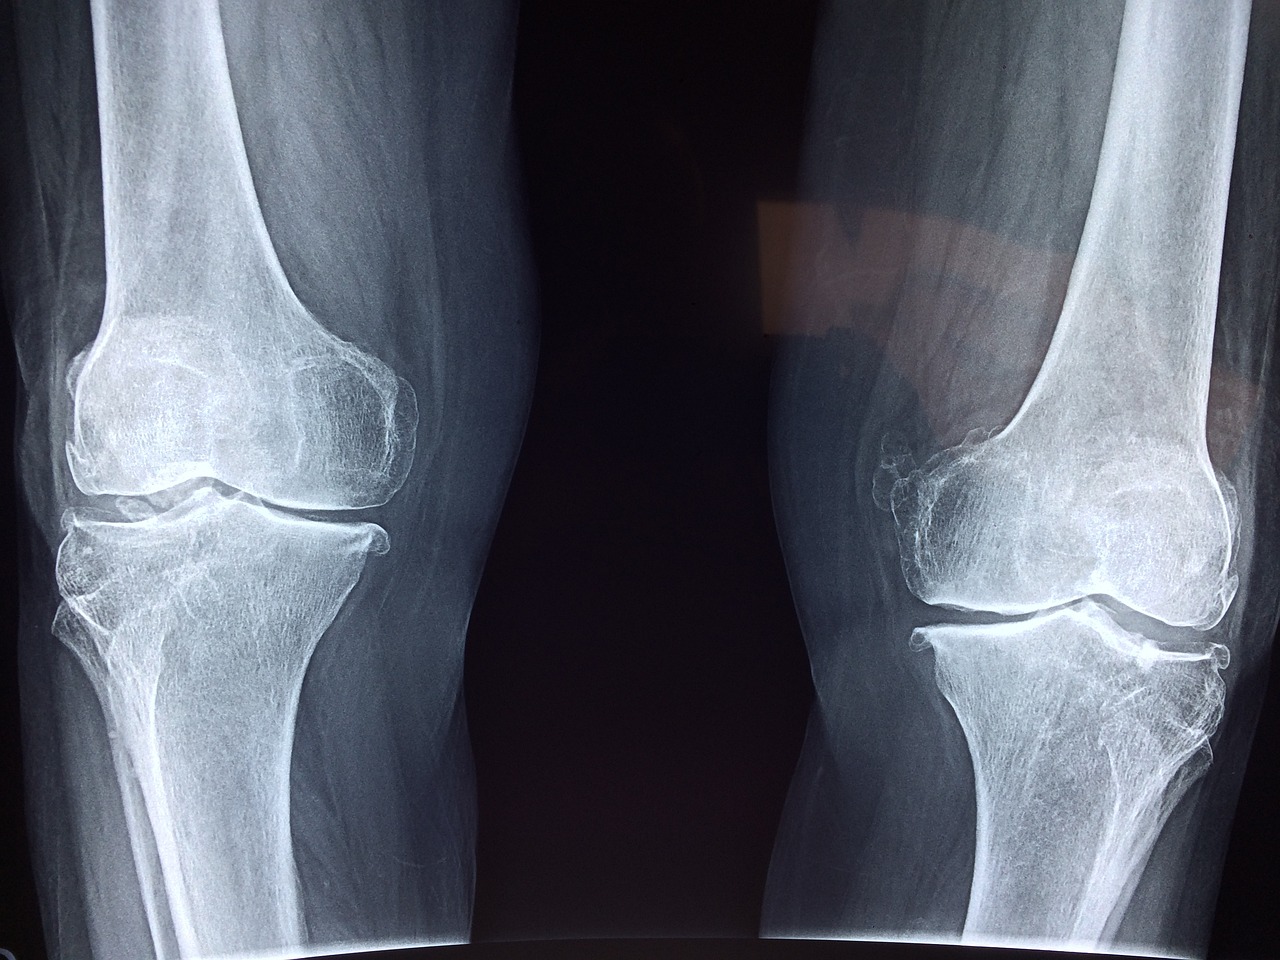

무릎 관절: 정렬 유지와 내외측 안정화 중점

해부학적 특징: 대퇴골-경골-슬개골로 구성된 복합 관절. 체중 부하가 크고, 인대 및 근육의 안정성에 의존도가 높음.

주요 적응증: 슬개골 추적 이상, 내측부인대 손상(MCL), 전방십자인대 손상(ACL), 수술 후 구축, 관절염 등

도수치료 기법:

- 슬개골 가동술(슬개골 상하/내외측 활주): 슬개골 유착으로 인한 통증 및 굴곡 제한 해소에 효과적.

- 경골 전방 활주(Tibial Anterior Glide): 대퇴골에 고정하고 경골을 전방으로 밀어 신전 범위 개선.

- 무릎 회전 조작: 외회전 제한 시 수동 조작으로 정렬 교정 및 관절 운동 재교육.

- 슬굴곡근 근막 이완: 반건양근, 반막양근, 대퇴이두근 등에 MFR 적용. 굴곡시 후방 당김 감소 효과.

※ 무릎은 통증의 위치가 다양한 만큼 슬개대퇴관절과 경대퇴관절, 인대 손상 유무를 반드시 구분해야 효과적인 접근이 가능합니다.